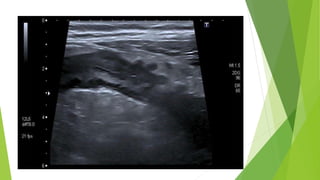

Abdominal ultrasound

Indications: may be performed as part of the workup for nonspecific

LLQ pain

Findings: outpouching from the colonic wall

Ultrasound abdomen

Indications

• Formal ultrasound is typically considered as an alternative to MRI in patients

with contraindications to CT

• Point-of-care ultrasound may be considered as an initial imaging modality and

can show findings of complicated diverticulitis (e.g., pneumoperitoneum, free

fluid, abscess formation).

Supportive findings:

diverticula with surrounding inflammation, abscess formation (detectable fluid),

bowel wall thickening